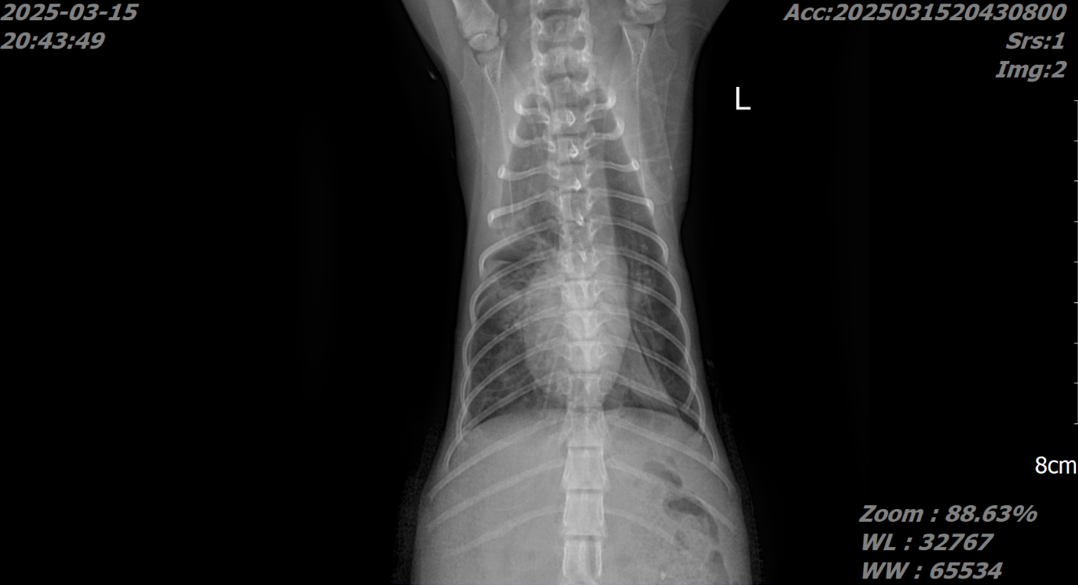

흉부 및 복부 X-ray를 촬영한 결과 흉수 및 복수가 모두 확인되었으며 심장 주변에 복강 장기들이 들어차면서 폐가 허탈되어 있는 모습을 확인할 수 있었습니다.

특히 폐 음영이 정상적으로 나타나는 부위가 없어, 호흡 곤란의 원인을 쉽게 확인할 수 있었습니다.

술후 X-ray에서 횡격막 경계가 뚜렷하고, 폐가 잘 팽창된 모습을 확인할 수 있었습니다.

가장 효과적인 진단 방법은 흉부 방사선입니다.

흉강 내 복강 장기 음영이 확인되거나 횡격막 윤곽이 소실되면 탈장이 의심됩니다.

특히 장의 가스 음영이 흉강에서 발견되는 경우 빠르게 확진을 내릴 수도 있습니다.

흉수가 동반된 경우 방사선에서는 잘 보이지 않을 수 있지만 초음파 검사를 통해 장기의 위치와 횡격막 결손을 확인할 수 있습니다.